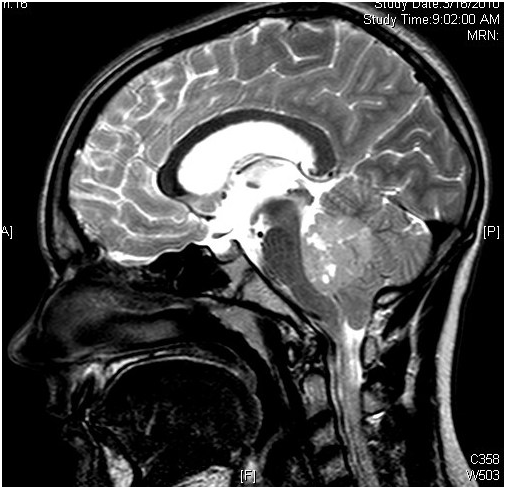

髓母细胞瘤 是一种癌性肿瘤,也被称为小脑原始神经外胚层肿瘤(PNET),它起始于颅底的大脑区域,即后颅窝,这些肿瘤往往会扩散到大脑的其他部位和脊髓...

髓母细胞瘤 是儿童较常见的恶性脑肿瘤,约占原发性中枢神经系统肿瘤的20%,约占后颅窝肿瘤的40%。它是一种发生于小脑的高级别(WHO IV级)胚胎性神经上皮...

髓母细胞瘤是18岁以下儿童中较常见的原发性中枢神经系统肿瘤,其较常见于四脑室。肿瘤浸润正常小脑组织,15%的病例浸润脑干。髓母细胞瘤患儿可表现...